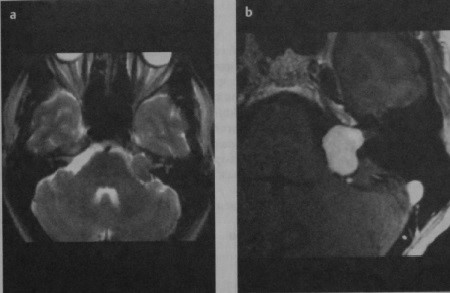

МРТ внутренних слуховых проходов в аксиальной проекции:

(а) Т1 до введения контраста.

(б) Т1 после введения гадолиния (обратите внимание на усиление сигнала от сигмовидного синуса и слизистой околоносовых пазух).

(в) Т2 (ликвор и глазные яблоки выглядят яркими),

а, мозжечок; b, сосцевидный отросток; с, четвертый желудочек; d, сонная артерия; е, сигмовидный синус;

f, улитка; д, сонная артерия; h, височная доля; i, мостомозжечковый угол (обратите внимание на слуховой и нижний вестибулярный нервы, которые входят во внутренний слуховой проход).